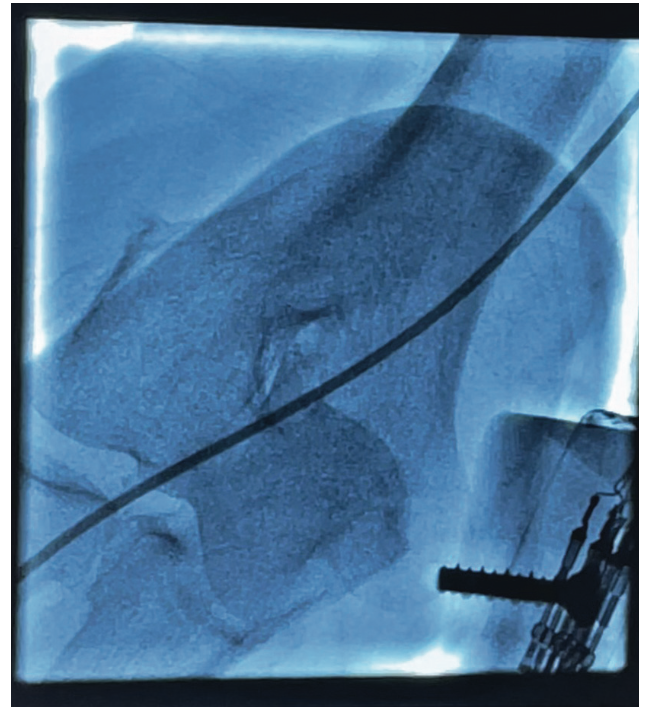

Unfortunately, the technologist would need to be close to the radiation source in order to help the patient, as well as have both hands in the primary radiation beam. After convening, we decided to attempt this technique with the use of minimal intermittent fluoroscopy and proper radiation protection. Regrettably, we did not have lead gloves available (which may or may not help with shielding, being in the primary beam). Under fluoroscopy, the kink was moved to the distal brachial artery very carefully while confirming the patient did not have pain in the arm. Once the catheter reached the distal brachial artery, under fluoroscopy, the technologist compressed the brachial artery with significant pressure proximal to the kink (Figures 3-4). The attending physician un-torqued and simultaneously pulled the catheter (Figure 5). Within seconds, we resolved the issue safely and efficiently. We aborted the RRA access site, cannulated the left distal radial artery (Figure 6), and completed the case.